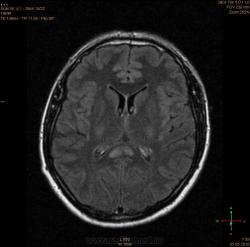

Болезнь Маркиафавы-Бигнами посмотри. На мой взгляд подходит.

Я заметил только 1 очаг в валике мозолистого тела. А для б-зни Маркиафавы-Бигнами более характерно несколько очагов дегенерации, в том числе и в полушариях.

Для болезни Маркиафава-Биньями считается патогноманичным центральная дегенерация мозолистого тела.

"Болезнь Маркиафава-Биньями – Болезнь Маркиафава-Биньями (Marchiafava, Bignami)- синдром при хроническом алкоголизме: энцефалопатия в форме центрального некроза corp.callosum (иногда и других комиссур). "

Я не против, действительно м.б. "Болезнь Маркиафава-Биньями". Особенно если нет динамики.

Но диф. ряд должен быть с опухолью. И если есть негативная динамика, тогда больше похоже на то, что в моз.теле не дегенерация, а "плюс-ткань" - обьемное образование. За октябрь сканов нет?

К сожелению первое исследование проводил ни я, а моя коллега, но контроль был за мной. Уже при первом исследовании, опухолевую принадлежность можно взять под сомнение, по скольку, даже допустим возьмем глиобластому это злокачественная опухоль из глиального ряда, т.е. должен быть тумор+отек=масс-эффект, ни того и не другого нет, ко всему этому сама локализация это валик мозолистого тела, а ни гемисфера, компенсации ни должно быть ни какой, клиника должно быть молниеносной и нарастающей.

Ко всему выше перечисленному могу добавить, видимо мою коллегу сомнения гложили, она провела исследование с контрастированием и получила тот же результат.